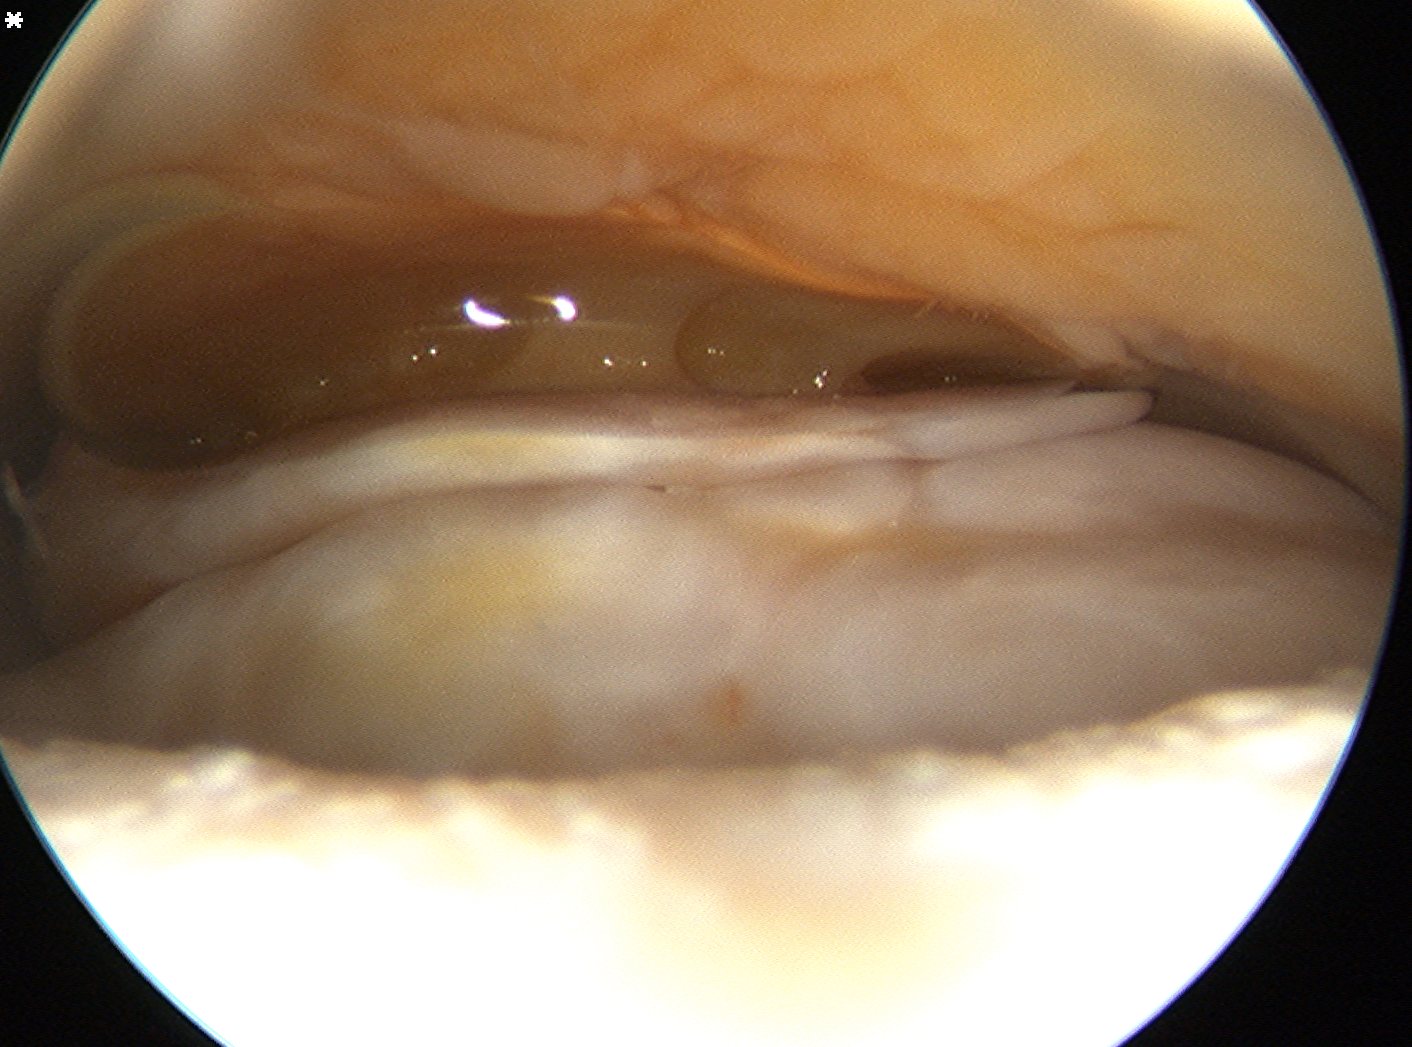

Glenohumeral joint assessment

Labrum

Anterior inferior labral tears

SLAP tears Posterior labral tears

Below equator

3 - 6 o'clock

Shoulder Arthoscopy Bankart Mobilisation Shoulder Sublabral foramen

posterior labrum